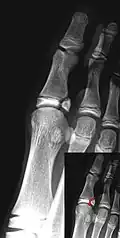

Salter–Harris III fracture of big toe proximal phalanx.

Salter–Harris IV fracture of big toe proximal phalanx.